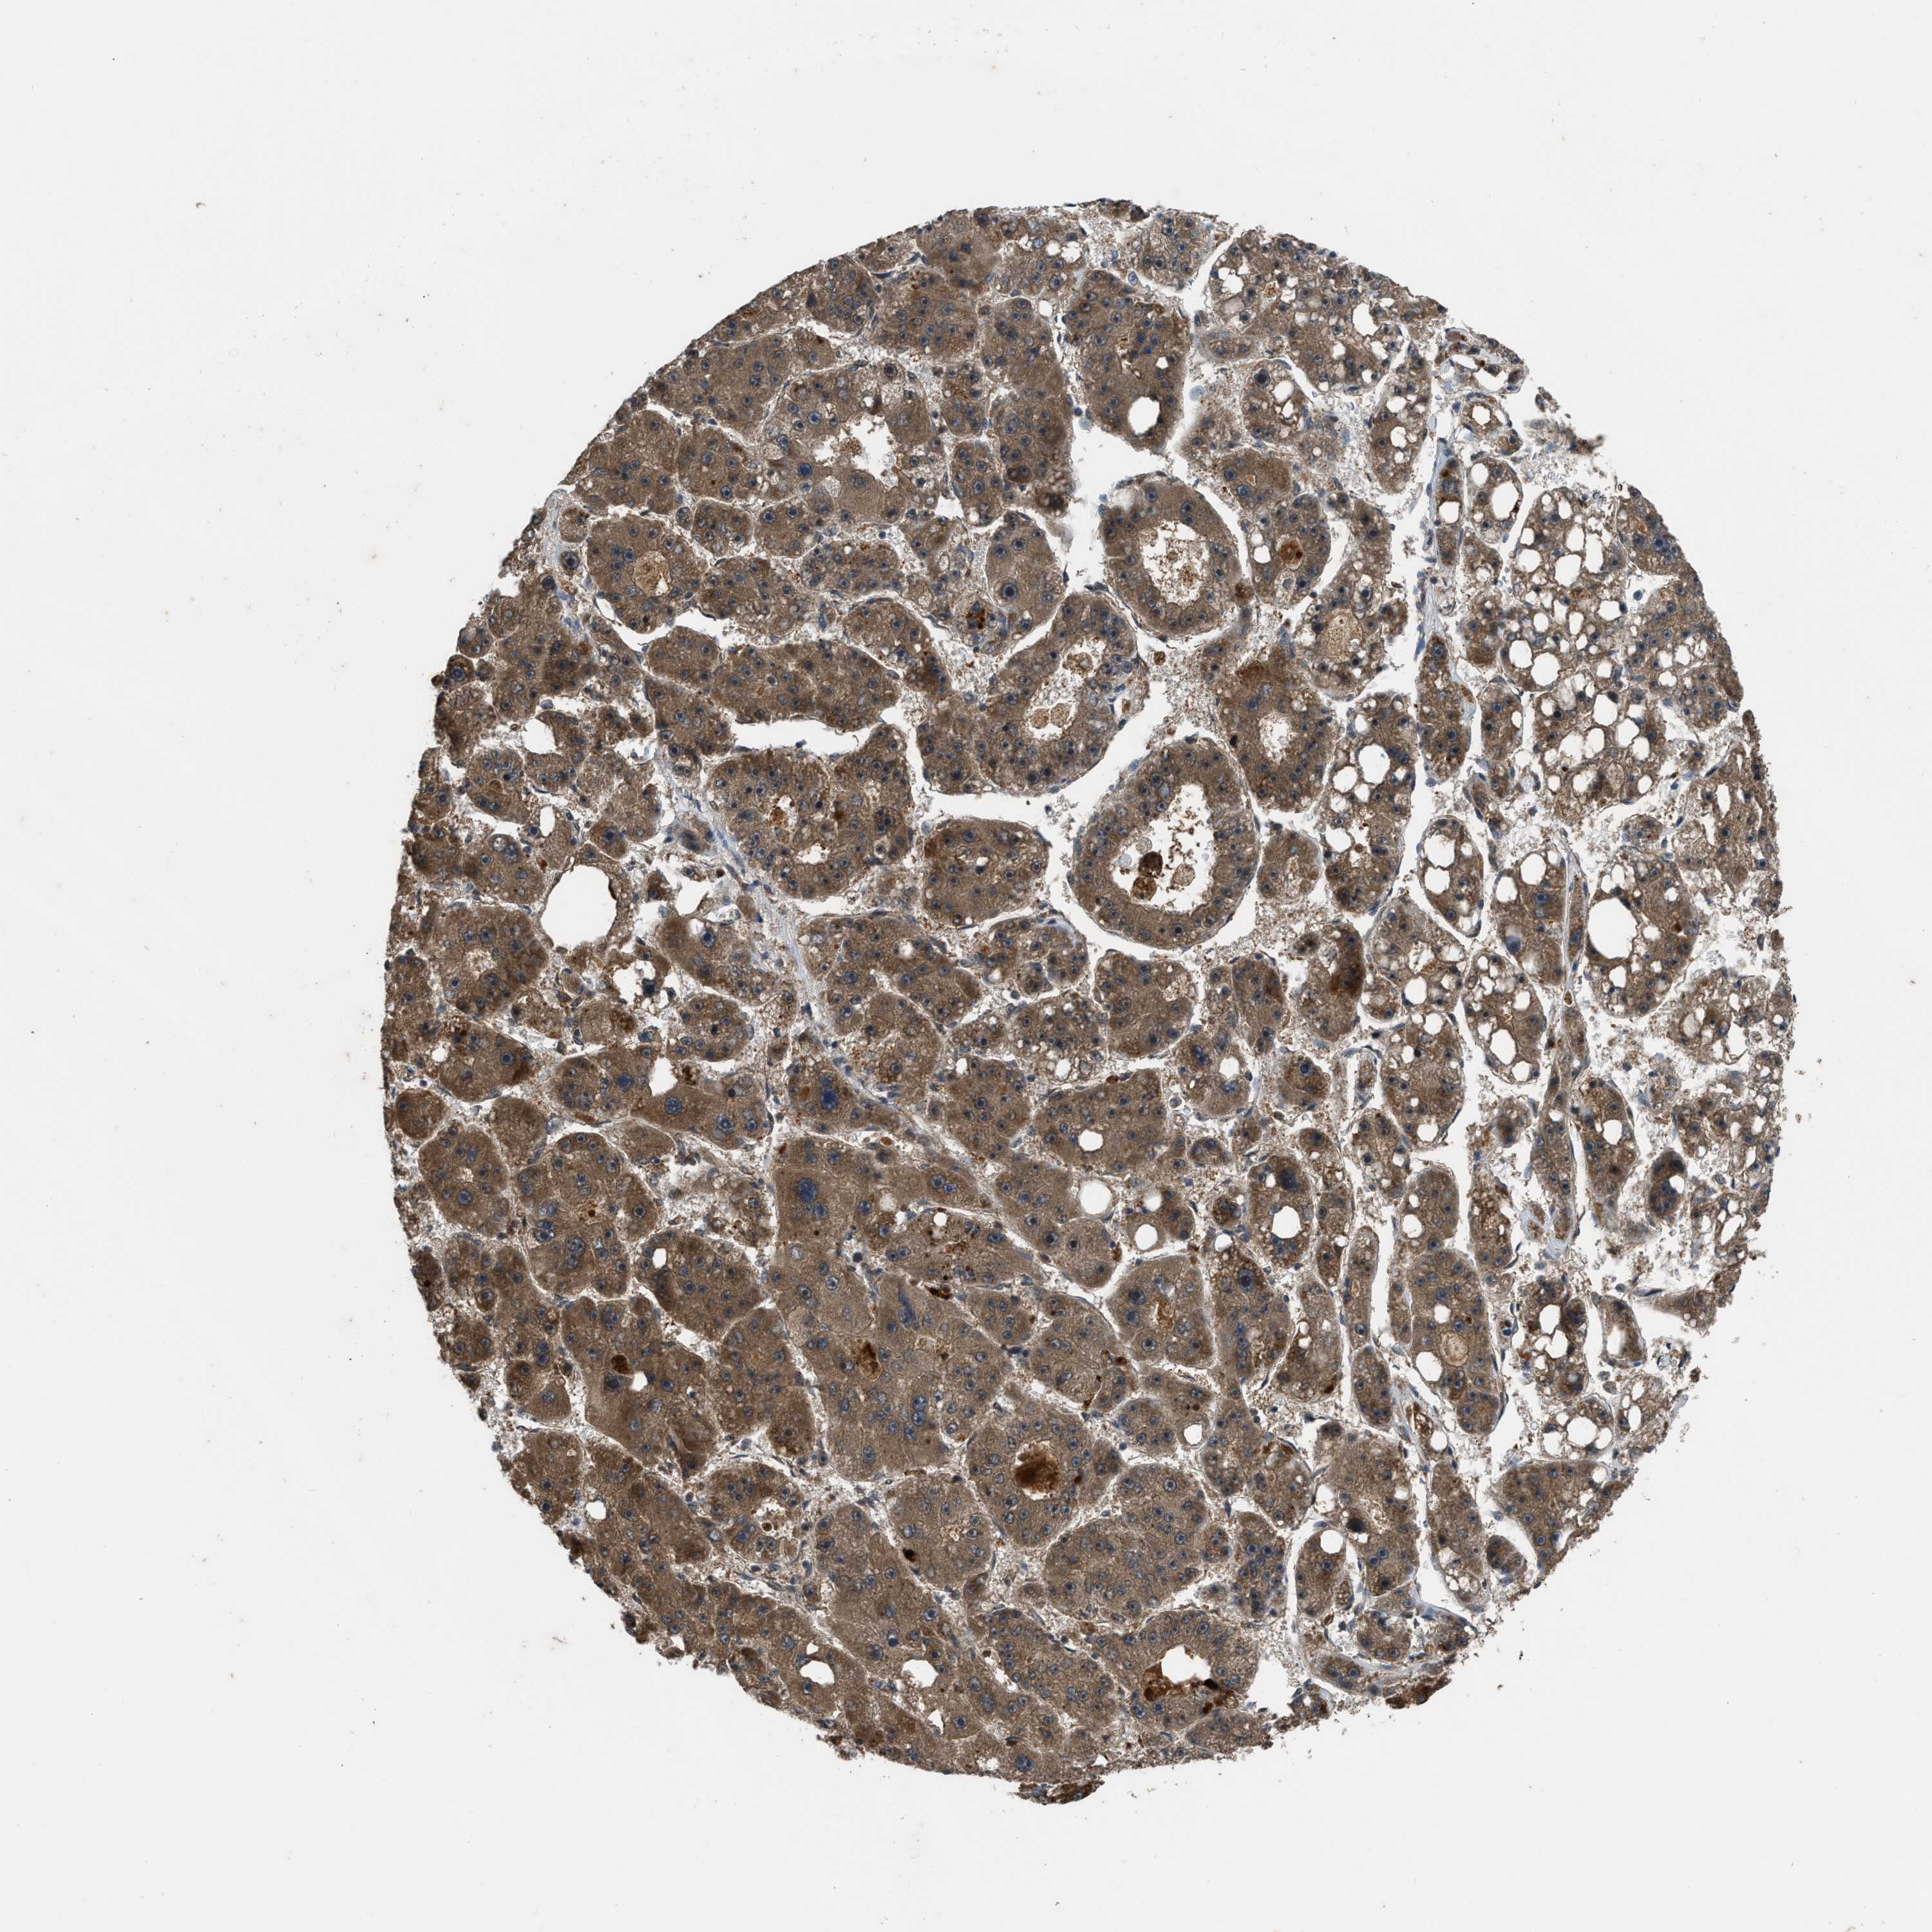

LIVER CANCER - Protein expressioni

A mouse-over function shows sample information and annotation data. Click on an image to view it in a full screen mode. Samples can be filtered based on level of antibody staining by selecting one or several of the following categories: high, medium, low and not detected. The assay and annotation is described here.

Note that samples used for immunohistochemistry by the Human Protein Atlas do not correspond to samples in the TCGA dataset.

Antibody stainingi

Antibody staining in the annotated cell types in the current human tissue is reported as not detected, low, medium, or high, based on conventional immunohistochemistry profiling in selected tissues. This score is based on the combination of the staining intensity and fraction of stained cells.

Each image is clickable and will lead to virtual microscopy that enables deeper exploration of all samples and also displays staining intensity scores, fraction scores and subcellular localization as well as patient and tissue information for each sample.

Antibody HPA018910

Antibody HPA018921

Antibody HPA018923

Staining

High

Medium

Low

Not detected

Intensity

Strong

Moderate

Weak

Negative

Quantity

>75%

75%-25%

<25%

None

Location

Nuclear

Cytoplasmic/membranous

Cytoplasmic/membranous,nuclear

Cholangiocarcinoma

Carcinoma, Hepatocellular, NOS